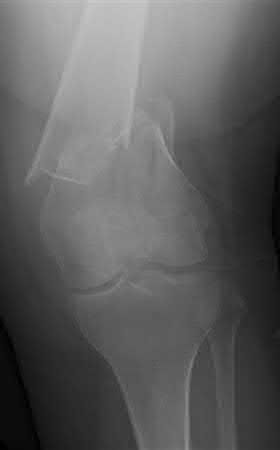

Buttress plating is most appropriate in which of the following clinical situations?

Figure A

Figure B

Figure C

Figure D

Figure E

Buttress plating is appropriate for a Shatzker Type I (see illustration C), as it can prevent collapse and axial deformity from shear or bending forces.

Figure B demonstrates an isolated medial femoral condyle fracture. Lateral locked plating is not an appropriate technique for this fracture.

The fracture shown in Figure B is an AO B type (partial articular fracture). This fracture is best treated with open reduction internal fixation through a medial approach, with lag screw and buttress plate fixation.

Figures A, C, D and E show supracondylar distal femur fractures that can be treated with ORIF with a fixed-angle device such as lateral locked plating.